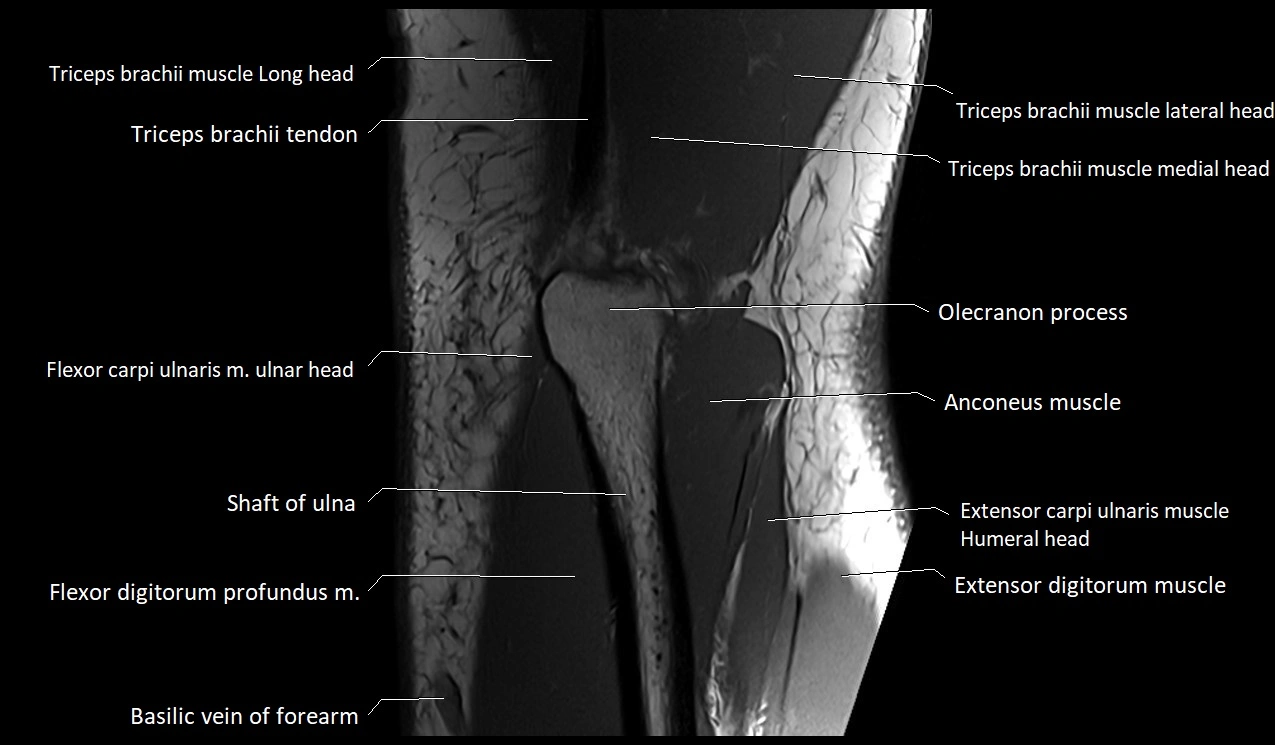

MRI image

image